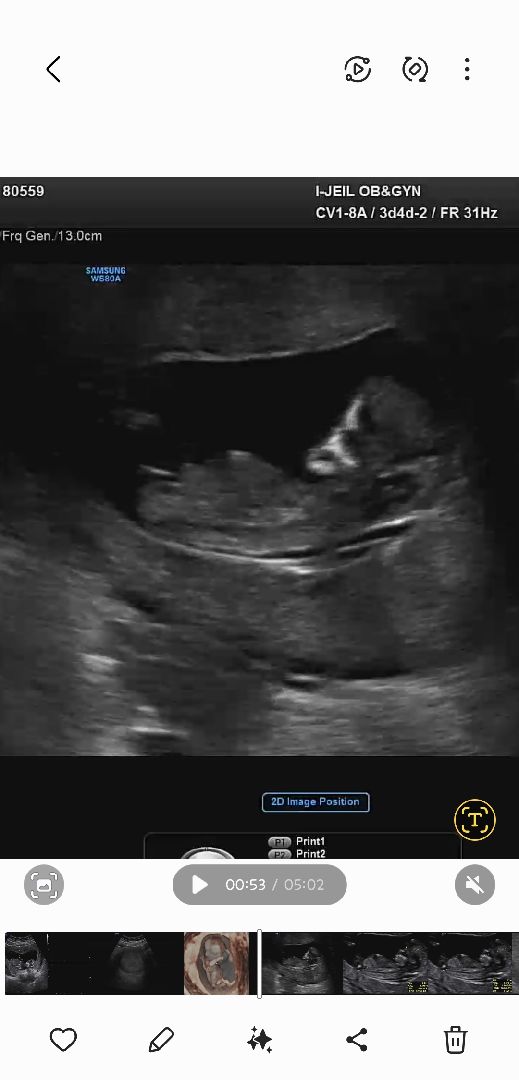

12주차 각도법 마구마구 참견해주세요♥️

12주차 기형아 검사했는뎅 각도법 참견해주세용 ㅎㅎㅎ